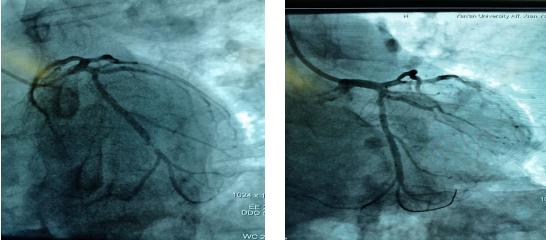

吴医生迅速到达心电图室,查看患者意识不清,心电图提示下壁心肌梗死、三度房室传导阻滞。立即给予阿托品、异丙肾上腺素提升心率,经积极抢救后患者心律逐渐恢复,意识逐渐清醒。“考虑患者是突发急性心梗引起的恶性心律失常,猝死风险极高,必须行急诊介入手术”,李新国责任总医师告知家属病情,同时启动应急预案,通知导管室做好急诊手术准备,应急电梯待命…家属同意手术后,立即前往导管室,实施急诊冠脉造影手术。造影结果证实LCX中远段95%狭窄,术中于病变血管处植入支架1枚,术后血流恢复,患者症状改善。在10余名医护人员3个多小时的紧急抢救下,终于我们战胜了死神。这一天,许久未晴的天空、阳光格外晴朗、明媚;这一天,北方的寒冬似乎也有了温度…